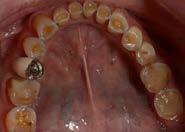

Paciente de 14 años y 8 meses, moti vo de consulta: “mi mordida no me gusta” el patrón esquelético es cla se II, hiperdivergente, clase II molar derecha y clase I molar izquierda, los caninos superiores en infraoclusión overbite disminuido, apiñamiento severo superior, moderado inferior, con los dientes 12 y 22 palatinizados, el 13 ectópico, con mordida abierta anterior, y las líneas medias desvia das.

Estudios de inicio fotografías intrao rales en la de frente se ven la línea media dental superior esta desviada

hacia la derecha y la línea media dental inferior a la izquierda, con mordida abierta anterior, el canino superior derecho se encuentra fuera del arco ( Figura 3 ), en la oclusal superior los inci sivos laterales palatini zados y paladar ojival profundo, en la lateral derecha una relación molar clase II y relación canina no determinable (Figura 4), en la izquier da una relación molar clase I y relación canina no deter minada.

172. Diciembre 2022 Corrección de mordida abierta anterior por deglución atípica Figura 3. Intraoral inicial de frente, la oclusal superior forma de arco triangular.